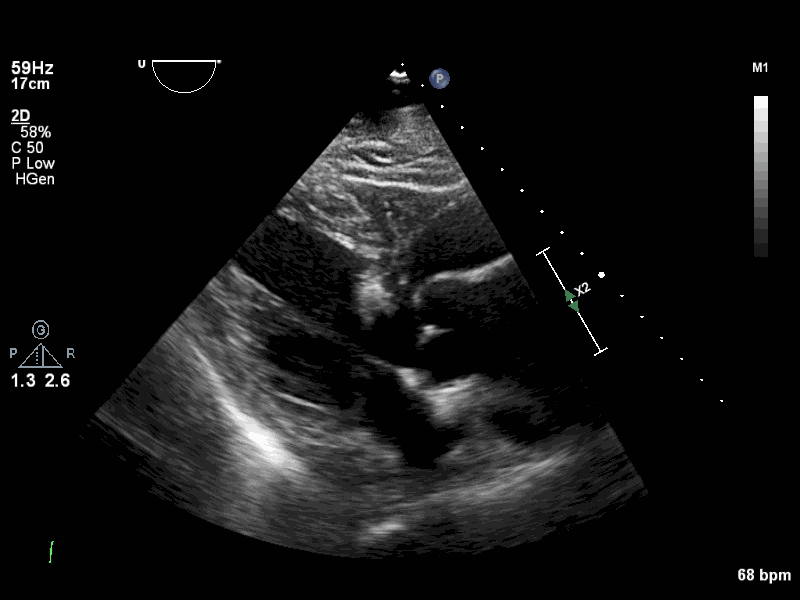

Visual Examples

PLAX Example 1 PLAX Example 2 PLAX Example 3 PLAX Example 4